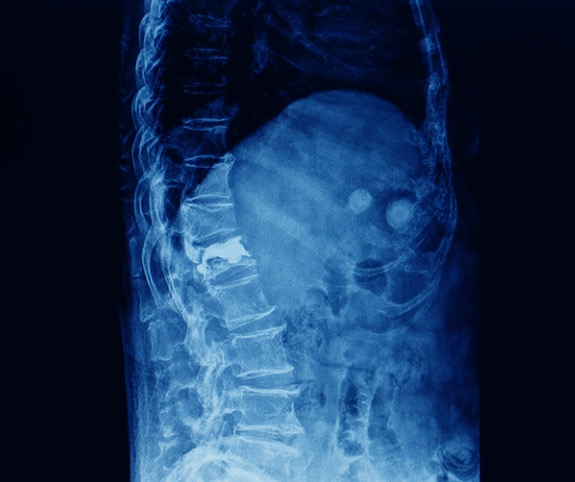

Αναφορικά με το πότε κάνουμε κυφοπλαστική, η επέμβαση ενδείκνυται όταν ο ασθενής παρουσιάζει οξύ ή υποξύ πόνο στη σπονδυλική στήλη που οφείλεται σε κάταγμα και δεν ανταποκρίνεται στη συντηρητική θεραπεία. Συνήθως, συνιστάται σε κατάγματα σπονδυλικής στήλης από οστεοπόρωση, τραυματικά κατάγματα με απώλεια ύψους, καθώς και σε ορισμένες περιπτώσεις συμπιεστικών καταγμάτων από μεταστατική νόσο. Η απόφαση λαμβάνεται εξατομικευμένα, με βάση τον τύπο του κατάγματος, την ηλικία του ασθενή και τη λειτουργικότητά του. Η έγκαιρη παρέμβαση μπορεί να μειώσει τον πόνο και να αποτρέψει περαιτέρω παραμόρφωση.

Η κυφοπλαστική πραγματοποιείται με τοπική ή γενική αναισθησία και περιλαμβάνει μικρή τομή στο δέρμα από όπου εισάγεται ειδική βελόνα στον πάσχοντα σπόνδυλο. Μέσα από αυτήν τοποθετείται ένα μικρό μπαλονάκι, το οποίο φουσκώνει προσεκτικά για να δημιουργήσει χώρο και να ανατάξει το κάταγμα. Στη συνέχεια, το μπαλονάκι αφαιρείται και στην κοιλότητα εγχύεται οστικό τσιμέντο υψηλής αντοχής, που σταθεροποιεί τον σπόνδυλο και μειώνει άμεσα τον πόνο. Η επέμβαση διαρκεί περίπου 30 λεπτά ανά σπόνδυλο και ο ασθενής επανέρχεται γρήγορα στις δραστηριότητές του. Η ταχεία κινητοποίηση μετά την επέμβαση μειώνει τον κίνδυνο επιπλοκών, ιδίως σε μεγαλύτερους ηλικιακά ασθενείς, και βοηθά στη γρηγορότερη επιστροφή στη φυσιολογική ζωή.

Τι Είναι Η Σπονδυλοπλαστική

Η σπονδυλοπλαστική είναι μια διαδερμική τεχνική που στοχεύει στη σταθεροποίηση των σπονδυλικών καταγμάτων μέσω άμεσης έγχυσης οστικού τσιμέντου μέσα στον σπόνδυλο. Δεν περιλαμβάνει μπαλονάκι όπως η κυφοπλαστική και δεν αποκαθιστά το ύψος του σπονδύλου, ωστόσο προσφέρει άμεση ανακούφιση από τον πόνο. Συνήθως, προτιμάται σε μικρότερα ή σταθερά κατάγματα όπου η αποκατάσταση ύψους δεν είναι απαραίτητη, καθώς και σε περιπτώσεις μεταστατικών βλαβών που απαιτούν γρήγορη και αποτελεσματική σταθεροποίηση. Πλεονέκτημά της αποτελεί ότι είναι μια πολύ σύντομη διαδικασία και το ότι η καταπόνηση του ασθενή είναι ελάχιστη.